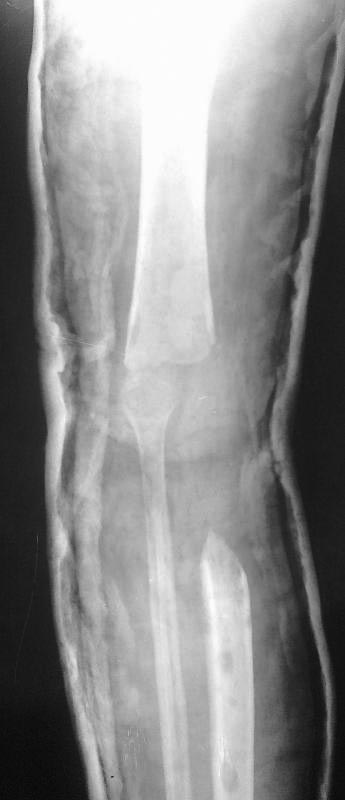

Пациентка 1972 года рождения. В сентябре 2012 года выполнена резекция

дистального отдела бедра и проксимального отдела большеберцовой кости.

В январе 2012 года оскольчатый внутрисуставной перелом проксимального

отдела большеберцовой кости. был выполнен накостный синтез пластиной.

Сопутствующая патология ВИЧ. Послеоперационный период осложнился

нагноением раны и последующим остеомиелитом большеберцовой кости.Больная

неоднократно оперировалась: удаление пластины,фиксация в аппарате,

остеонекрэктомии. Из-за недостатка опыта не выполнили в свое время

мышечную пластику с закрытием раны, в результате инфекция

прогрессировала, распространилась на коленный сустав. В сентябре 2012

выполнена остеонекрэктомия (резекция мыщелков бедра, проксимальной 3

большеберцовой кости), рану закрыли, конечность фиксировали простым АВФ

и лангетой. На данный момент имеет место укорочение конечности до 10 см,

отека,гиперемии,ран,свищей нет, чувствительность и движения в стопе

сохранены, пульс на артериях стопы хороший. Имеет место анемия (87),

аппарат снят, конечность фиксирована лангетой, больна уверенно

передвигается на костылях. Планируется восстановить опорную конечность

используя  проксимальный отдел малоберцовой кости для замещения дефекта

закрыто в АВФ (что-то вроде операции Гана), возможно с удлинением

конечности.